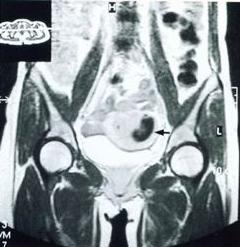

撤退性子宮出血手術為了減少撤退性出血的量,可在肌肉注射黃體酮時,同時注射丙酸睪酮(一種雄性激素製劑),每日25~50毫克,共3天。如果血量仍然很多,則應讓患者臥床休息,口服或肌肉注射維生素K、止血敏、維生素C、止血芳酸等一般止血藥,甚者可以輸葡萄糖液、輸血。撤退出血時不應再用雌、孕激素製劑。

生育年齡妊娠婦女的撤退性子宮出血。多屬於排卵型,大都發生於產後或流產後的恢復期中。一般來說,育齡婦女的性腺軸應該處於穩定狀態,發生異常的子宮出血多數是器質性病變,如炎症、贅肉、子宮肌瘤、子宮內膜異位等,應及時到醫院檢查確診。